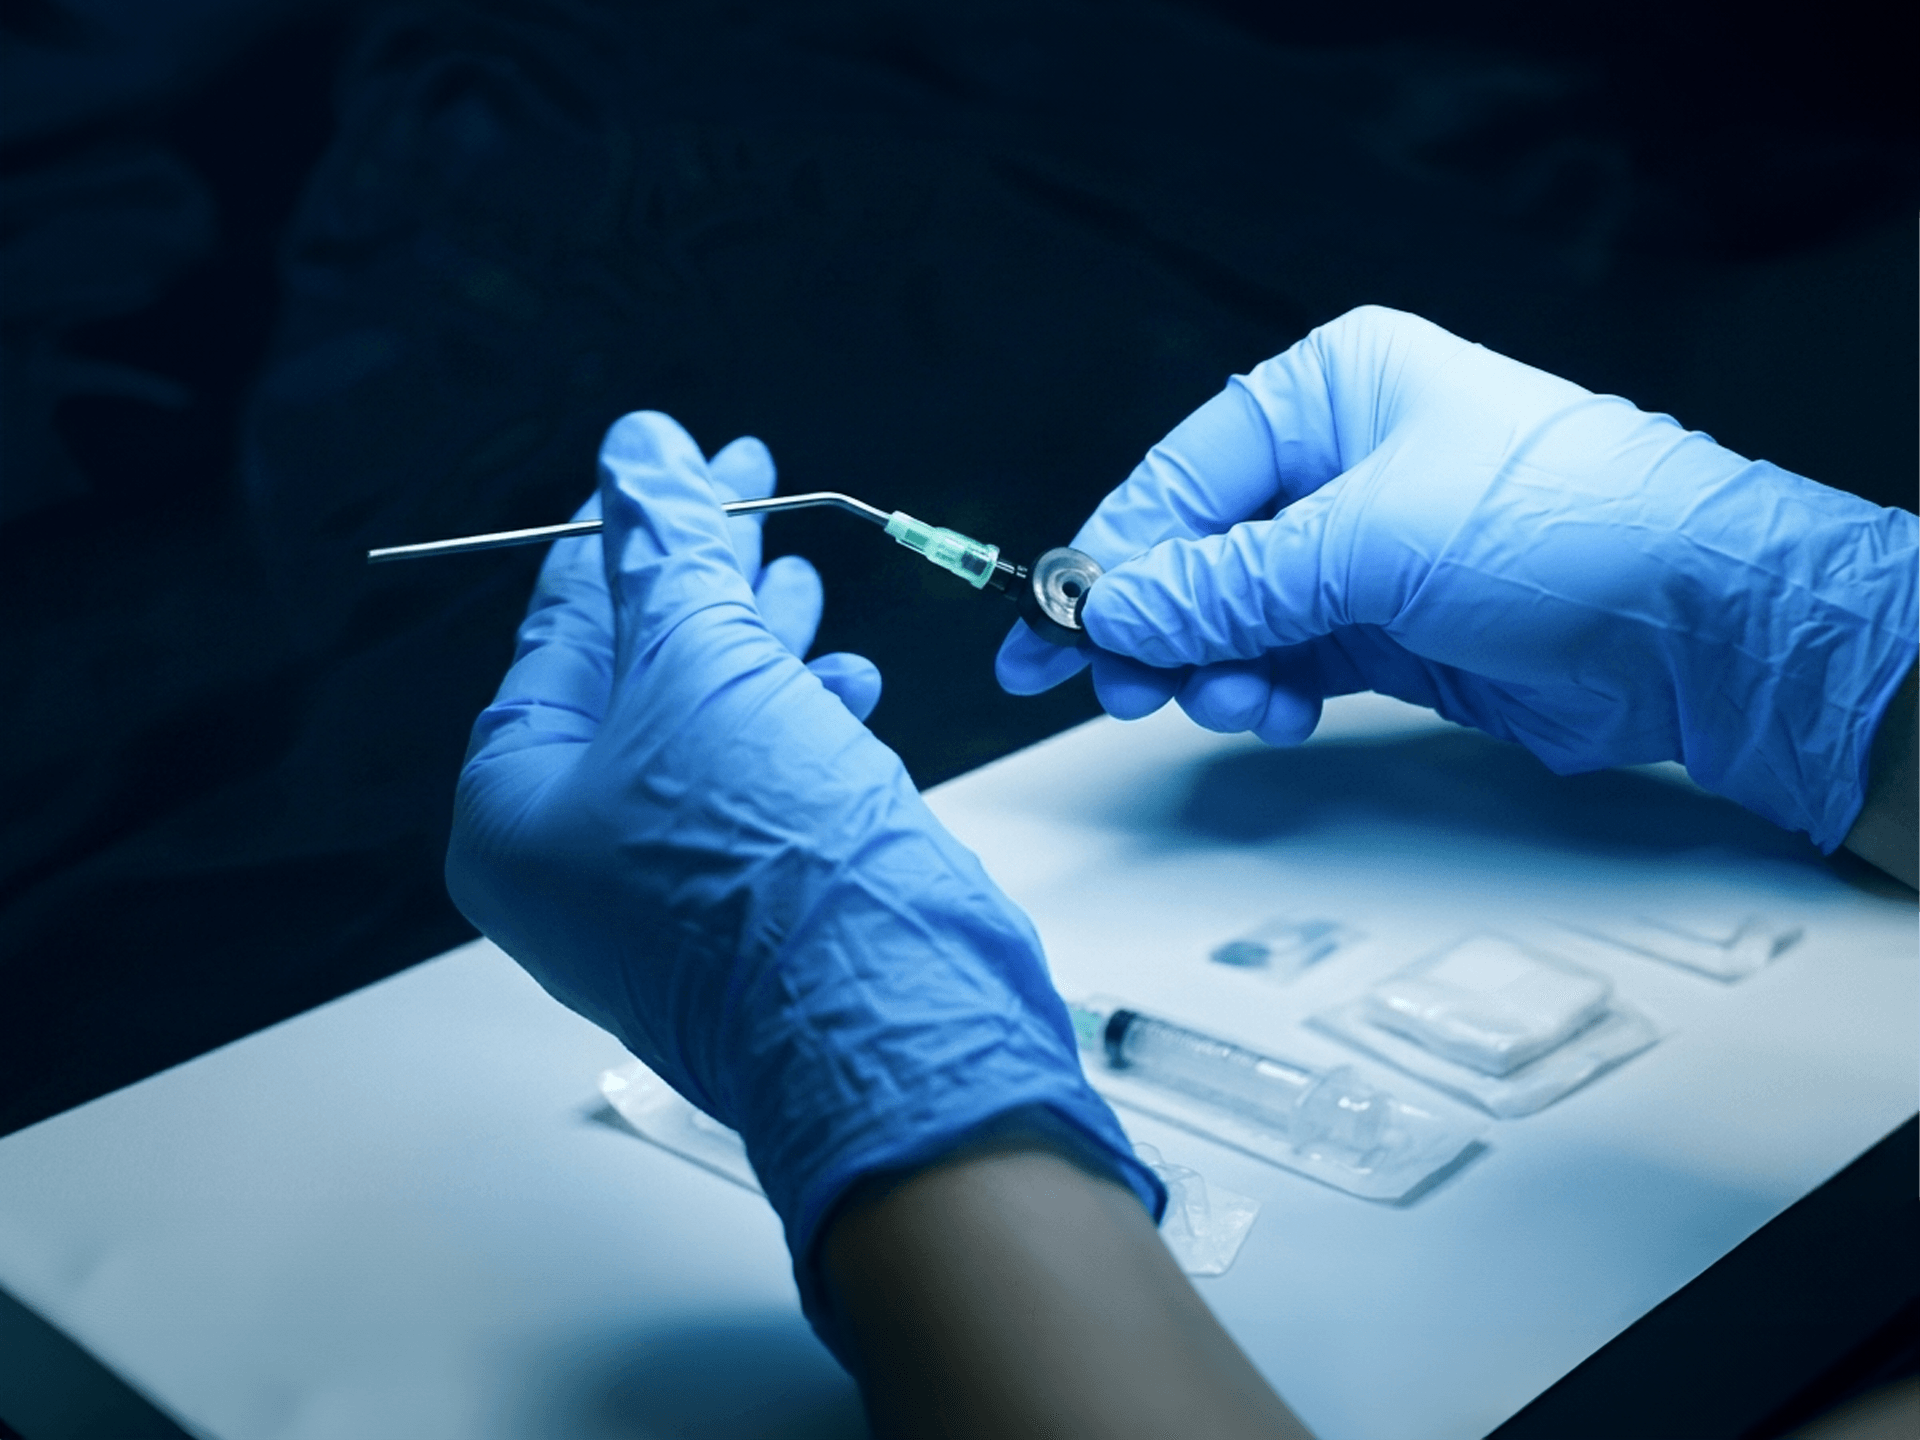

We design medical devices that support patient positioning, clinician ergonomics and procedural workflow in interventional radiology, cardiology and neuroradiology. Devices also available for otology, rhinology and sterilisation.

Since 2003, we’ve been designing and manufacturing purpose-built medical devices that support clinicians, simplify workflow, and enhance patient care.

We focus on quality, performance and reliability to help support better outcomes for both patients and healthcare professionals. Our design engineers interact early with clinicians to ensure our products integrate seamlessly with existing workflows.